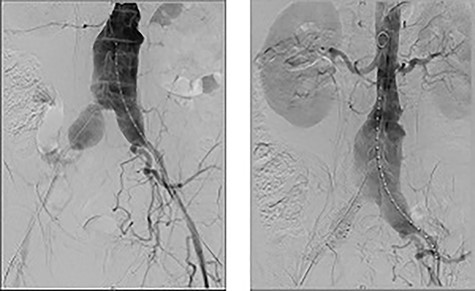

Extensive workup for infective and autoimmune aetiologies such as tuberculosis, syphilis, Q-fever and human immunodeficiency virus (HIV) were negative and serum IgG-4 levels normal (Table 2). He underwent an endovascular aortic aneurysm repair (EVAR) with bilateral iliac branched devices (IBD) during his initial presentation, and his on-table completion angiogram demonstrated good flow through the grafts with no endoleak (Fig. 4).

On table completion angiogram demonstrating good flow through the stent graft and satisfactory flow through renal arteries and iliac branching device with no endoleak.

Post-aortic stenting, a percutaneous US-guided biopsy of the para-aortic fibrosis was obtained for histopathological evaluation. Results reported non-specific fibrous tissue with chronic inflammation and no features of granulomatous inflammation or malignancy. He was subsequently discharged on Day 8 post-EVAR and on 30-day follow-up, a repeat CTA showed all grafts remained patent with no evidence of endoleak or evidence of aneurysmal enlargement. He subsequently had his ureteric stents removed, with continued normalization of renal function, and was referred to a rheumatology specialist for ongoing management of suspected systemic IgG-4 related disease.